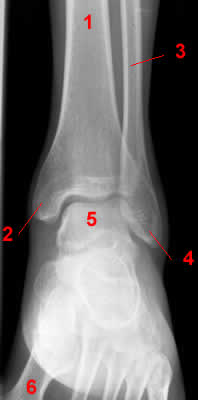

Голеностопный сустав.

1, Б/берцовая кость.

2, Медиальная лодыжка.

3, Малоберцовая кость.

4, Латеральная лодыжка.

5, Таранная кость.

6, Плюсневые кости.